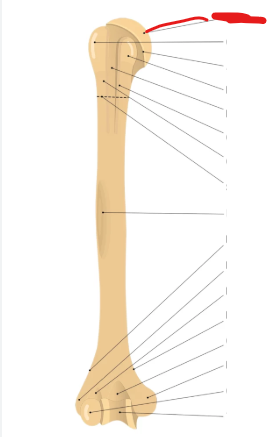

pectoral girdle and upper limb

head

lesser tubercle

greater tubercle

deltod tuberosity

olecranon fossa

medial epicondyle

lateral epicondyle

trochlea

surgical neck